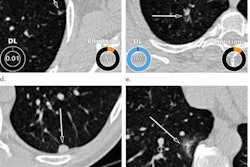

The researchers applied the AI-Rad Companion (Siemens Healthineers) software to 100 consecutive patients who received noncontrast chest CT exams at their institution. They then compared the algorithm's performance for identifying five findings -- pulmonary lesions, emphysema, aortic dilatation, CAC, and vertebral compression fractures -- with the original radiology reports signed by attending cardiothoracic radiologists.

| Aortic dilatation | 96.3% | 25.9% | 81.4% | 100% | 0.89 | 0.63 |

The better results for AI in identifying aortic dilatation and CAC were statistically significant (p < 0.001 and p = 0.005, respectively). The radiology reports also showed that the interpreting radiologist outperformed the AI in identifying pulmonary lesions and vertebral compression fractures (p = 0.024 and p < 0.001, respectively). The performances were statistically comparable for identifying pulmonary emphysema (p = 0.064).